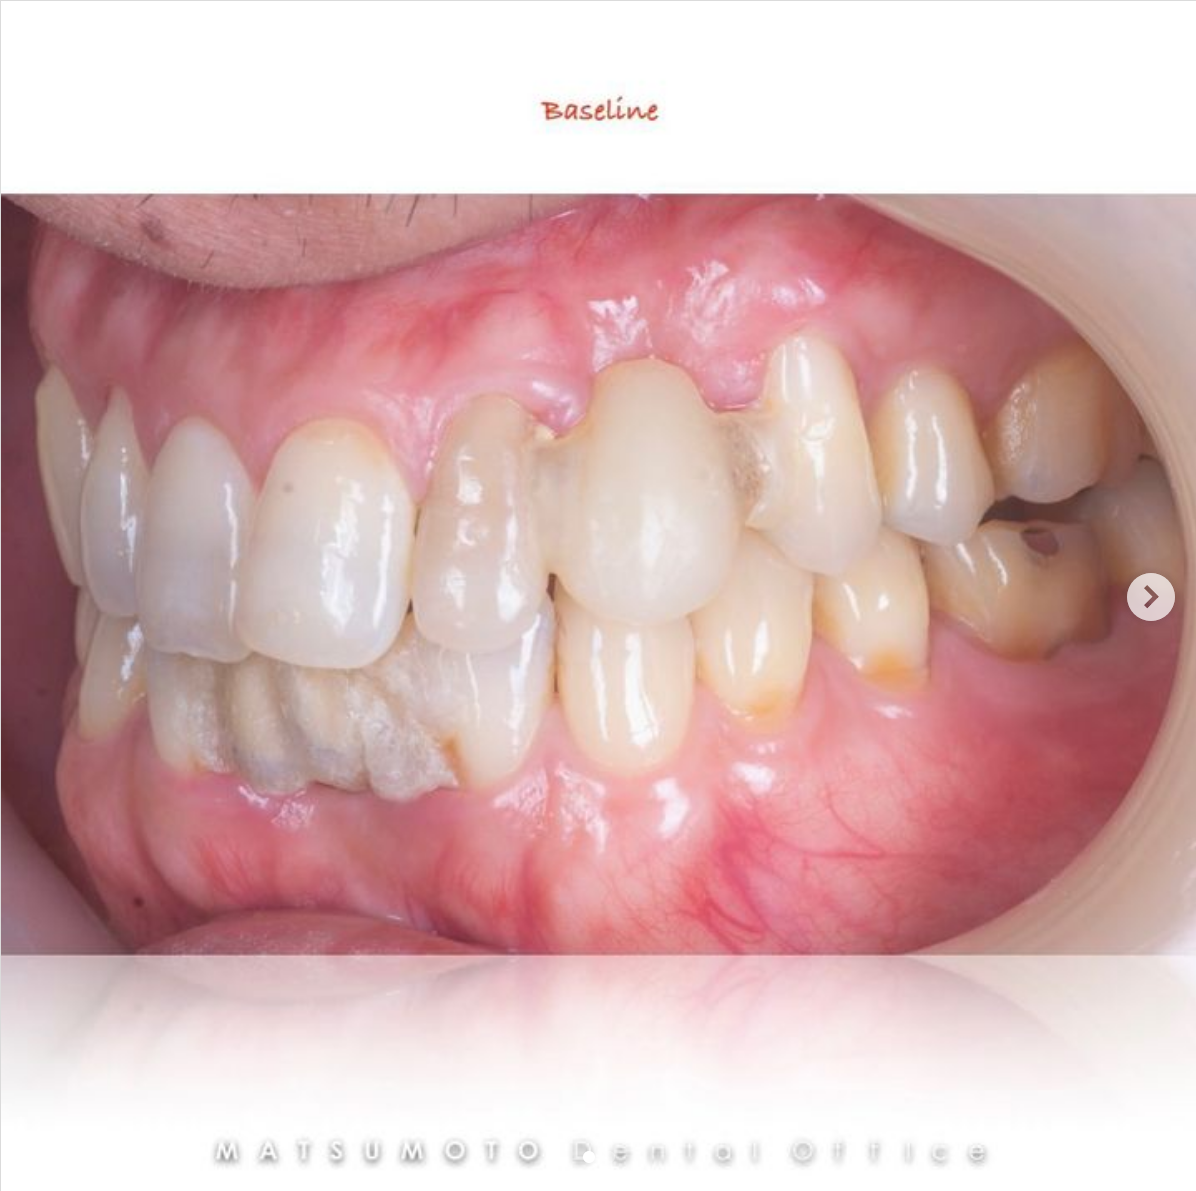

術前の診査診断

術前写真

上顎:前歯以外は保存不可のな状態である。

下顎:下顎は奥歯は保存不可能な状態であった。

パノラマX線

上顎:痛いとの訴えがあった左上の奥歯は、上顎洞炎が起きている。

下顎:奥歯は骨の吸収が波及しており、保存不可能である。

All-on-4を終えて

最終補綴

上顎:セラミックレイヤードフルジルコニアインプラントブリッジ

下顎:治療しないで経過観察とした。

治療のリスクと副作用

治療期間:約半年

治療費:¥3,500,000(税込)

リスク:噛み合わせを大きく変えているので、しっかりメンテナンスしていかないと将来的に噛み合わせが不安定になるリスクがあります。しかし仮歯でしっかりと状態を確認しすることでリスクをできるだけ回避することができます。